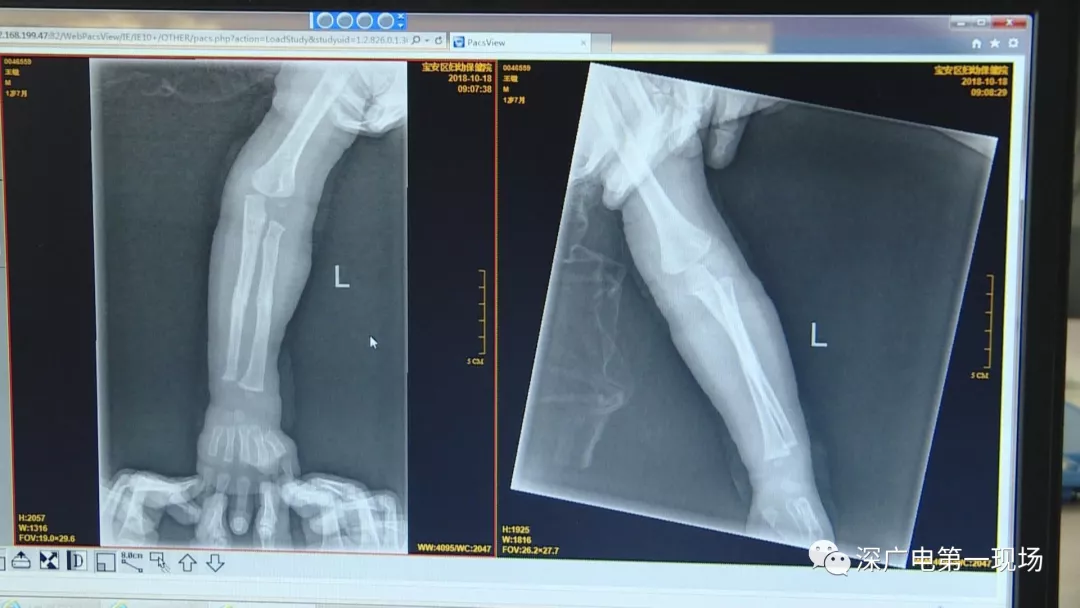

因禍得福!1歲男童摔傷送院 醫(yī)生竟從胸片中發(fā)現(xiàn)了這個…

胳膊摔骨折胸片里發(fā)現(xiàn)異物